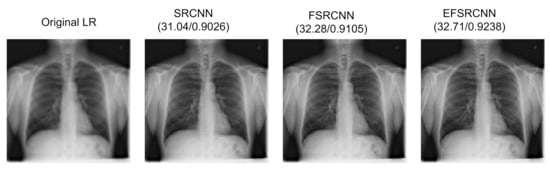

| Metrics | SRCNN | FSRCNN | EFSRCNN | |

|---|---|---|---|---|

| Region of Interest | PSNR SSIM | 32.83 dB 0.9268 | 33.06 dB 0.9283 | 32.24 dB 0.9341 |

| Whole region | PSNR SSIM | 31.04 dB 0.9026 | 32.28 dB 0.9105 | 32.71 dB 0.9238 |